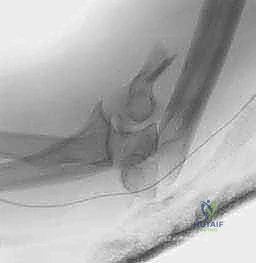

6. إصلاح العظم المقطوع والإغلاق

إذا تم استخدام تقنية قطع الناتئ الزندي (Osteotomy)، يتم الآن إعادة العظم إلى مكانه وتثبيته بقوة باستخدام تقنية شريط الشد (Tension Band Wiring) بأسلاك معدنية قوية، أو باستخدام صفيحة ومسامير خاصة.

يتم غسل الجرح جيداً بمحاليل معقمة، ويتم وضع أنبوب تصريف (Drain) لمنع تجمع الدم، ثم تُخاط الأنسجة والجلد بعناية فائقة لتقليل الندبات (بفضل خبرة الدكتور هطيف في الجراحة الميكروسكوبية التجميلية). وتوضع جبيرة خلفية خفيفة.